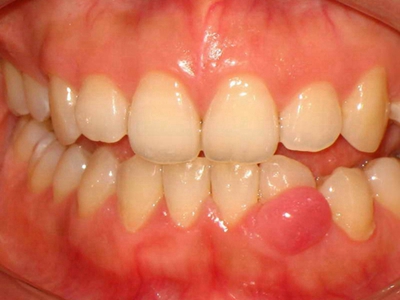

牙龈炎是发生于牙龈组织的炎症,患者可出现牙龈出血伴肿胀、发红、正常形态改变和偶尔不适等症状。本病主要由口腔卫生状况差导致,包括口腔不洁、牙菌斑等,诊断依据临床检查,治疗包括专业牙齿清洁和加强家庭口腔卫生。

牙龈炎可先引起牙齿与牙龈之间的沟(龈沟)加深,然后牙龈充血,炎症围绕一个或多个牙齿,伴牙龈乳头肿胀和易出血。一般无痛,可自行消退,也可维持轻度炎症数年。